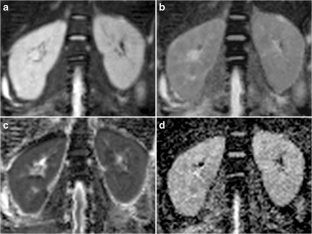

Fig. 2